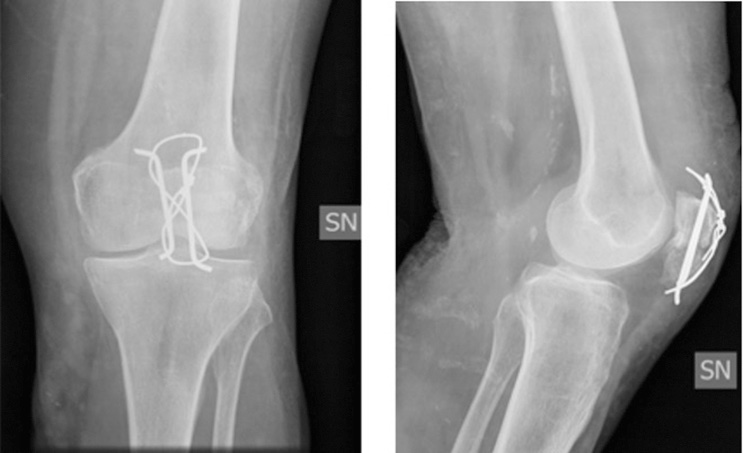

Pertanto, una delle tecniche più utilizzata è il “tension band wiring” o cerchiaggio a 8. Questa procedura viene normalmente eseguita con il paziente supino con il ginocchio flesso di 30°. L’incisione in questo caso è pre-rotulea, i frammenti più grandi vengono ridotti usando una pinza di riduzione appuntita. A questo punto, si procede con l’infissione di 2 fili di K paralleli, perpendicolari alla rima di frattura. Controllato il posizionamento esatto dei fili K, si procede all’inserimento di un filo di cerchiaggio bloccato ad 8 che va a stabilizzare la frattura (Fig. 2).